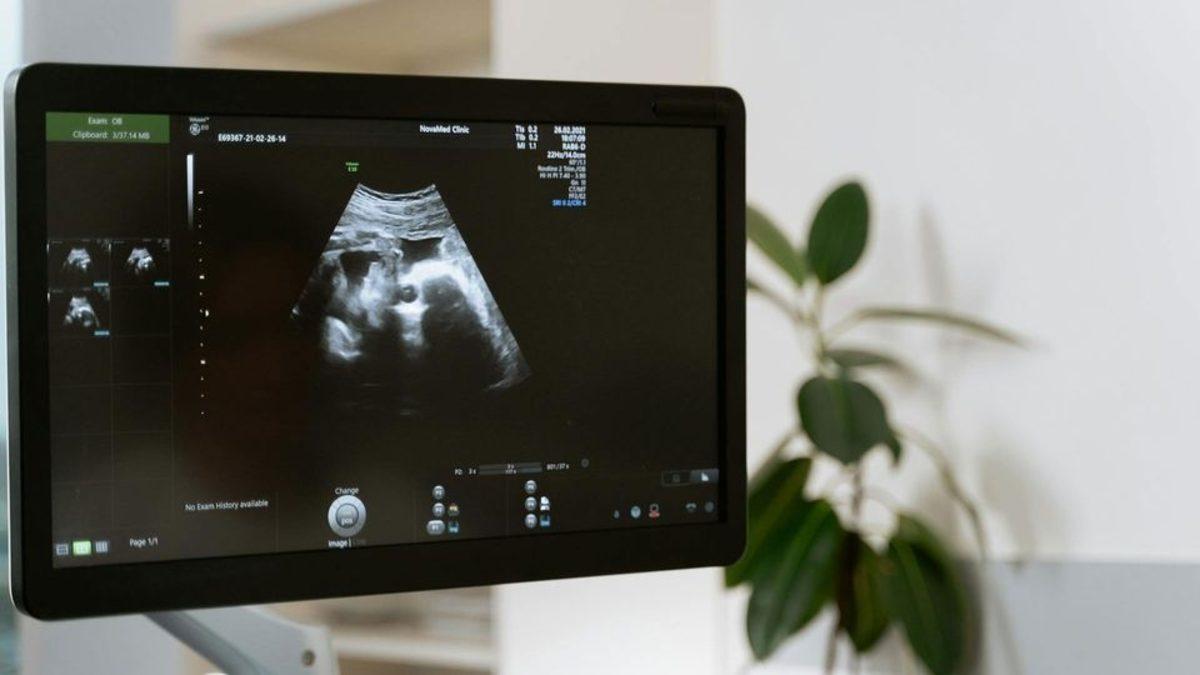

Anne karnındayken gelişmekte olan fetüse ilaç verildi

ABD Gıda ve İlaç Dairesi (FDA), bu çalışma için tek seferliğine Evrysdi markalı ilacın doğum öncesi kullanımına onay verdiler. Bu hastalıkta en etkililerinden biri olarak bilinen Risdiplam isimli ilaç, anneye verilmeye başlandı. Doktorlar, doğum yapmadan önce altı hafta boyunca her gün bir doz ilaç verdiler. Doğumun ardından ise direkt bebeğe oral yoldan ilaç verildi. Tüm bunların sonucunda bebek, 2,5 yaşına gelmesine rağmen herhangi bir semptom belirtisi göstermeden hayatta kalmayı başardı.